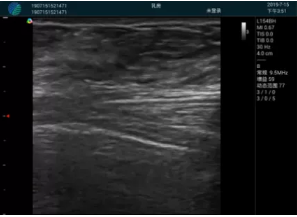

可視化穿刺引導(dǎo)

M20實(shí)時(shí)引導(dǎo):向包塊后方間隙注射利多卡因

清晰顯示腺體內(nèi)低回聲快影,邊界清晰,包膜較光滑

確定進(jìn)針路徑并實(shí)時(shí)監(jiān)測抽吸針與腫塊位置關(guān)系

抽吸針進(jìn)入腫塊內(nèi)部進(jìn)行旋切

抽吸過程中可見腫塊明顯縮小,并根據(jù)腫塊位置改變針道位置

抽吸旋切后再進(jìn)行超聲復(fù)查,原腫塊區(qū)域未見殘留組織及出血